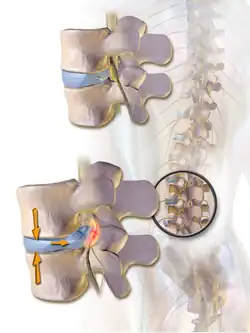

Une hernie discale est une lésion atteignant le rachis et caractérisée par le déplacement d'une partie d'un disque intervertébral hors des limites de sa situation normale. En principe, cette hernie est la conséquence d'une ouverture dans l'anneau fibreux laissant passer une partie du noyau pulpeux, plus mou, à l'extérieur de cet anneau. La hernie discale est habituellement en rapport avec une lésion dégénérative du disque liée à l'âge, pouvant être favorisée par un traumatisme ou des efforts répétés. Le plus souvent la hernie est localisée au niveau postérolatéral, ce qui est favorisé par la présence du ligament longitudinal postérieur dans le canal vertébral[1].

La hernie postérieure est favorisée par la compression de la portion antérieure du disque lors de la flexion antérieure du tronc, ce qui entraîne la poussée du noyau pulpeux contre la portion postérieure de l'anneau fibreux. Ceci peut aboutir à la rupture de l'anneau fibreux et au déplacement progressif du contenu du noyau pulpeux à travers cette lésion vers le canal vertébral. La compression d'un nerf spinal du fait d'une hernie entraîne des symptômes décrits plus bas.